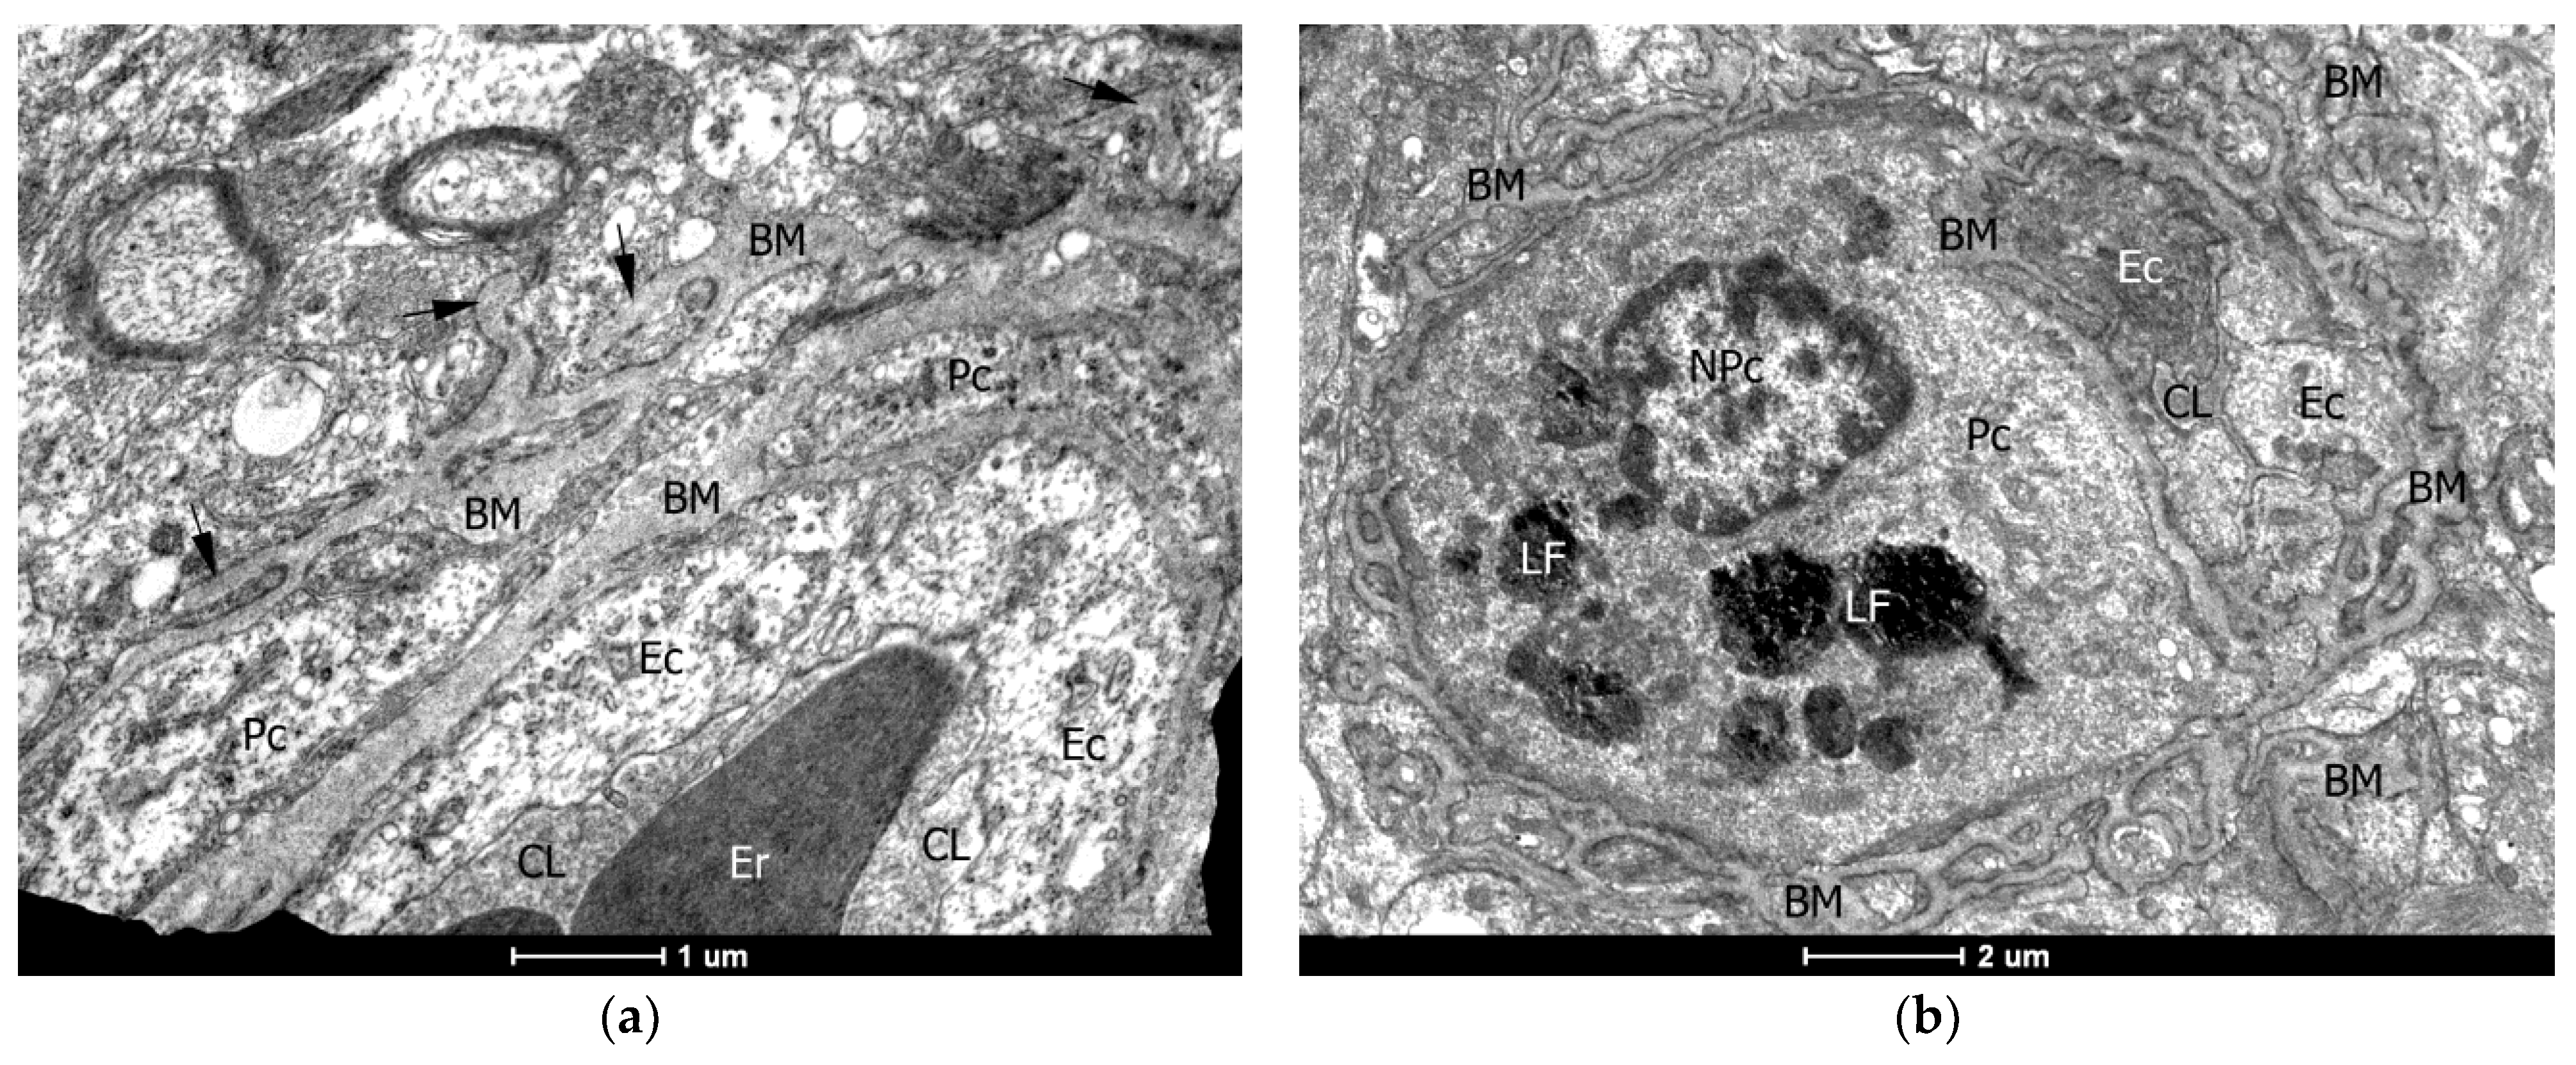

2.4. Ultrastructural (TEM) Examination of the Vascular Wall of the Capillaries

4.2. Transmission Electron Microscopy (TEM)